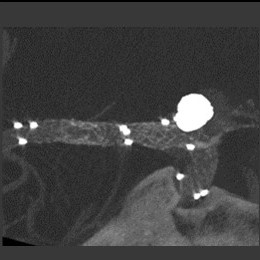

大動脈弁狭窄症(BAV施行時の大動脈造影)

TAVI術後造影

大動脈弁計測画像